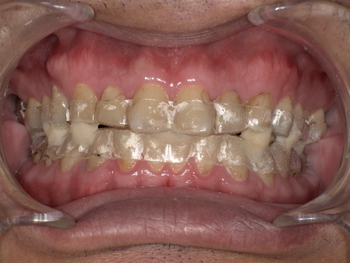

無呼吸症候群のマウスピース装着後

<驚きの改善結果>

いびきと無呼吸の改善: マウスピースを使用し始めてから、奥様からいびきを指摘されることがほとんどなくなったとご報告いただきました。

睡眠の質の向上: 「夜中に目が覚める回数が減り、朝までぐっすり眠れるようになった」とAさんご自身も効果を実感されています。

日中のパフォーマンス回復: 「日中の眠気がなくなり、仕事に集中できるようになった」と、生活の質が大きく向上しました。

この症例からわかるように、たった一つのマウスピースが、睡眠の質を劇的に改善し、日々の生活、ひいては命に関わるリスクを低減する大きな一歩となるのです。